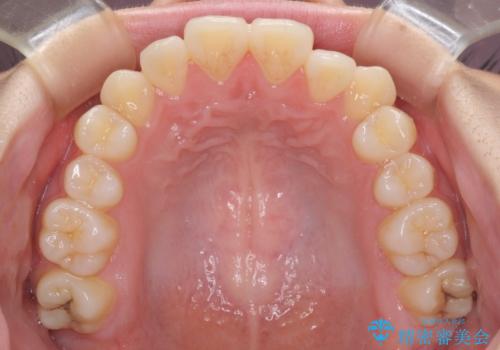

カリエール・ディスタライザーとインビザラインを用いた八重歯の改善

- 前歯の叢生と上顎左右の八重歯を気にして来院された患者様です。

奥歯の咬み合わせを見ると、左側は上顎が下顎に対して相対的に前方にあり、上下の前歯が接触していない状態でした。

咬み合わせを改善するためには、左側上顎臼歯を後方に移動させた咬み合わせにする必要があります。

インビザライン単体で改善することも可能性もありますが、インビザライン単体で達成する可能性が低いと考えられたため、カリエール・ディスタライザーという補助装置を併用して、より確実性を上げることとしました。

奥歯の咬み合わせを改善しながら、並行してインビザラインで歯列を整えることとしました。

カリエールディスタライザーを併用したことで、左側臼歯の咬み合わせを確実に改善させることができました。